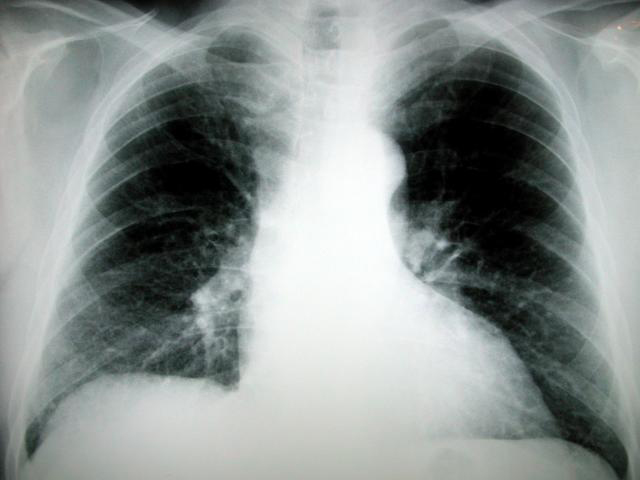

Un nuovo test molecolare sviluppato dalla University of California di San Francisco potrebbe dare agli studiosi la capacita’ di predire meglio la mortalita’ nelle prime fasi post-operatorie degli interventi per il cancro ai polmoni.

La ricerca, pubblicata sul ‘Journal of American Medical Association’ (JAMA), ha mostrato che i test messi a punto dal gruppo di studiosi identificano i pazienti con una alta probabilita’ di ricorrenza anche del tumore polmonare non a piccole cellule. La ricerca ha coinvolto 1439 pazienti da Stati Uniti e Cina che si sono sottoposti a chirurgia negli ultimi 15 anni. I risultati hanno mostrato che gli scienziati potrebbero accuratamente dividere i pazienti, anche se si trovano nelle prime fasi del cancro, in gruppi a basso, medio e alto rischio di morte basandosi sull’attivita’ di soli 14 geni trovati nei loro tumori. Le informazioni prognostiche sono ottenute da analisi molecolari della biologia di un tumore e superano significativamente quelle che vengono ottenute dai test prognostici tradizionali che si basano su esame al microscopio del tumore. (AGI) .